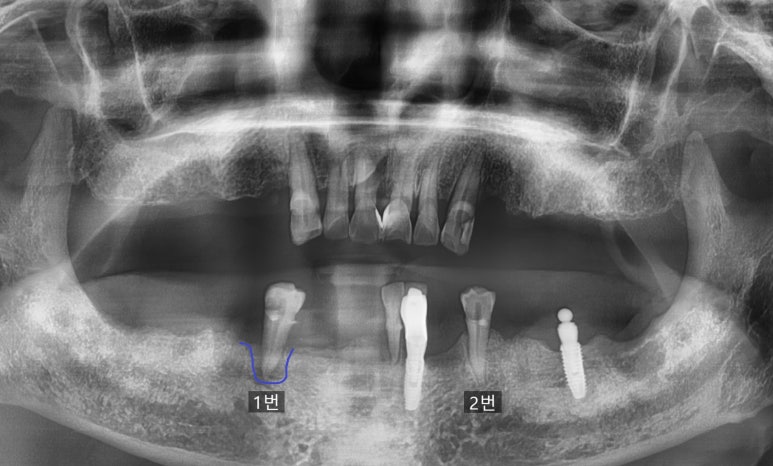

환자분이 처음 오셨을 때의 파노라마사진입니다.

환자분은 부분틀니를 이미 가지고 있는 상태였고

임의상 파노라마에 제가 1번, 2번으로 표시한 것에 대해 말씀드리자면

1번, 2번 모두 최악의 경우 발치를 설명드렸지만

파노라마 상 2번 표시한 치아의 상태

1번의 경우는 치아 주변 잇몸뼈가 많이 녹아

파노라마 상에 까맣게 보이는 부위 = 뼈가 녹은 부위가 보이는 상태

& 치아를 잡아주는 뼈가 녹아 많이 흔들리는 상태였고

2번의 경우는 위의 카메라로 찍은 사진처럼 치아가 엄청 많이 썩어있었지만

치아 주변의 뼈는 비교적 많이 녹지 않았고 치아도 흔들리는 상태는 아니었기 때문에

1번의 경우는 발치 후 뼈가 어느정도 찰때까지 기다렸다가 임플란트를 하는 것이

2번의 경우는 만약 임플란트를 한다면 발치하면서 임플란트를 하는 것이

가능할 수 있다 하겠습니다.